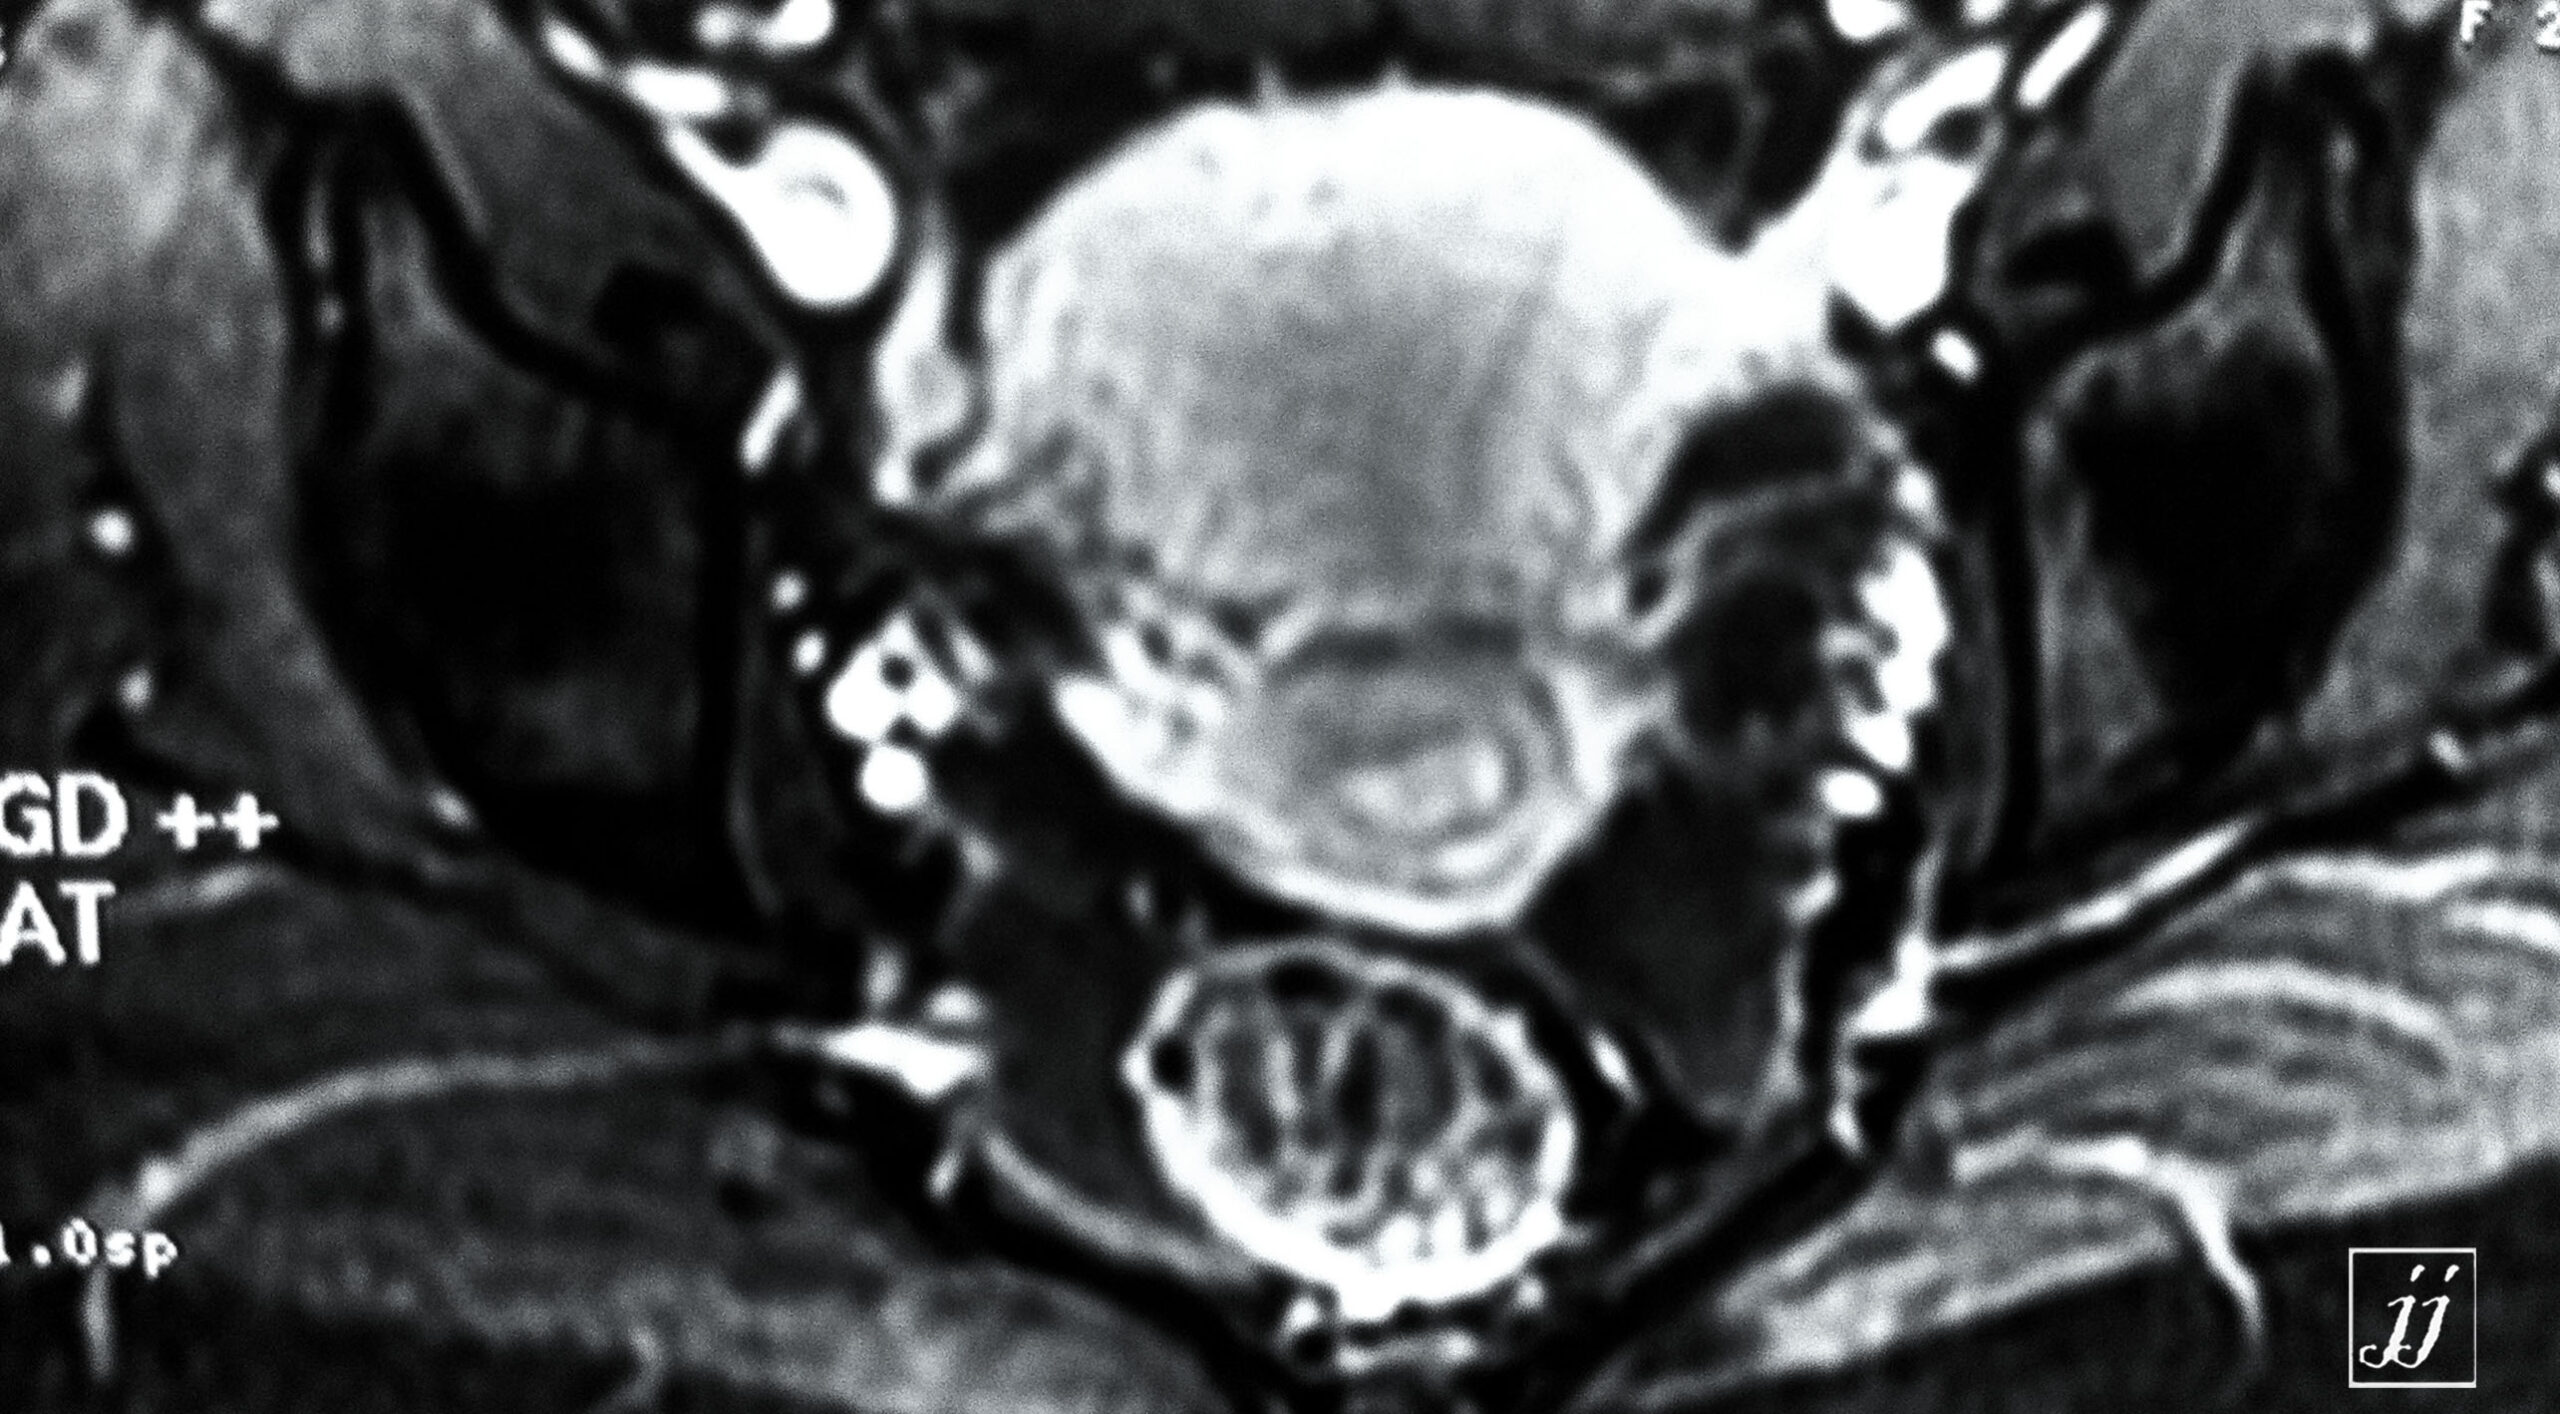

Abdomen- left side endometriosis vs dermoid cyst (8)